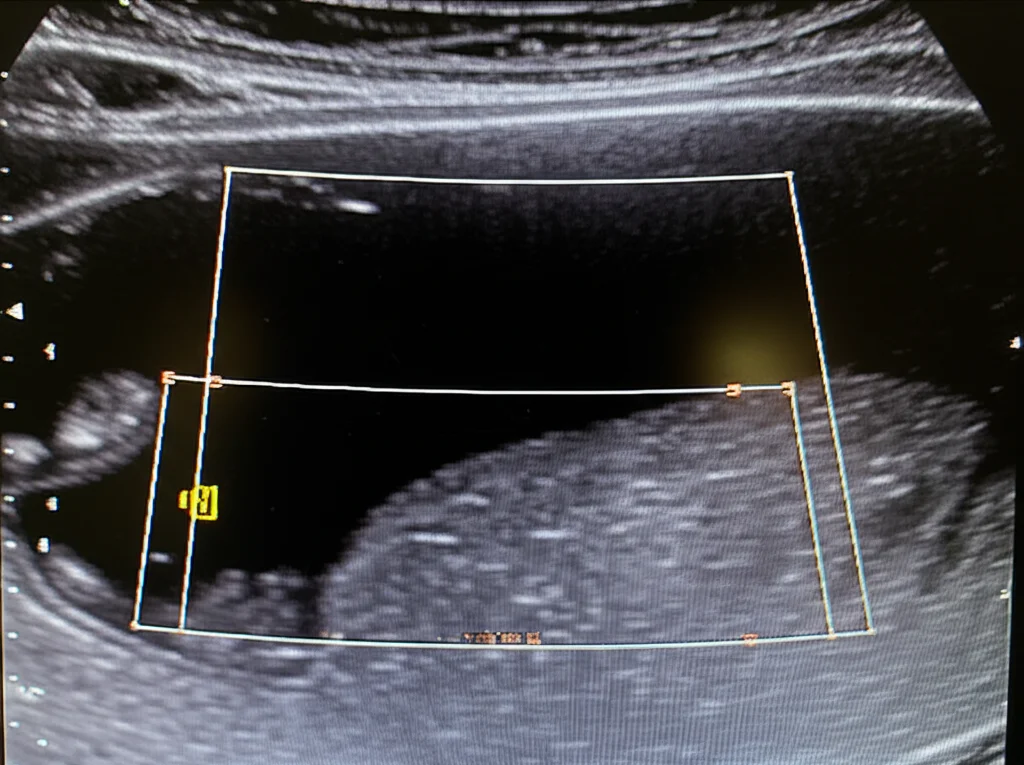

This study I stumbled upon is all about using POCUS to look specifically at the thickness of the quadriceps femoris muscle – that’s the big muscle on the front of the thigh. Why the quadriceps? Well, it’s a big one and easy to get to, even when kids are tucked up in bed in the PICU. The idea was to see if measuring this muscle thickness could help us figure out how well-nourished these kids are when they first arrive and track how things change over their first week.

The plan was simple but smart: use POCUS to measure the thickness of the quadriceps muscle on Day 1 (when they arrived), Day 3, and Day 7. They took a few measurements each time and averaged them out. They were careful to use the same technique and even had a specialist radiologist doing the measurements to keep things consistent.